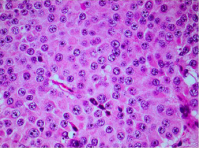

He had distal pancreatectomy and splenectomy. His histology showed normal tubular and acinar morphology within a vascular stroma. There was modest nuclear pleomorphism with some chromatin aggregation, prominent nucleoli and abundant granular cytoplasm (Figure 5).

Figure 5 Tumor in high power modest nuclear pleomorphisim, prominent nuclei with abundant granular cytoplasm.

On histology, Glucagonomas show no striking characteristics. Mitotic figures and nuclear atypia are rare. Immunostaining may be positive for glucagon- containing granules, indicative of their alpha cell origin. Many glucagonomas are pleomorphic with cells containing granules that stain for other peptides, most frequently pancreatic polypeptide. On electron microscopy, benign tumors are usually fully granulated, whereas malignant cells have fewer granules [5].